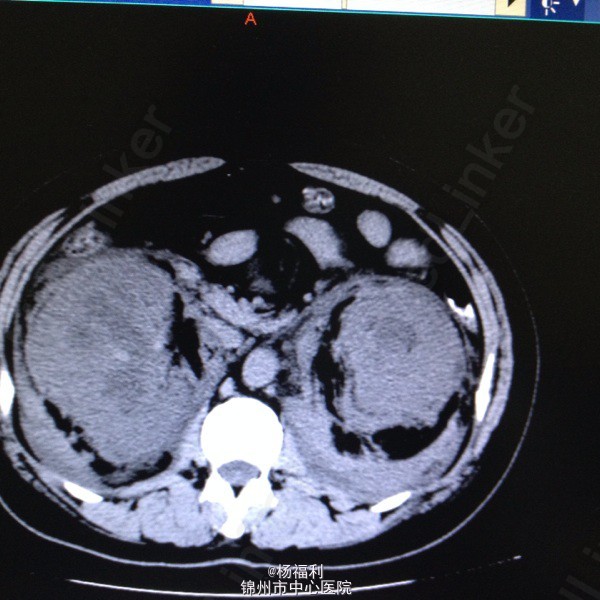

44岁女患。为消化科我会诊患者。 现病史:以上腹痛9小时为主诉入院。无发热及寒战、噁心未呕吐,无腹泻及黑便。 既往史:双眶炎性假瘤2年,口服激素治疗,并补钾。

查体:上腹部压痛,无反跳痛、右侧压痛明显,右肾区叩击痛,左肾区轻叩击痛,双输尿管走形区无压痛。 辅助检查;泌尿系彩超:双肾积水。 血白细胞:9.99*10^9。 肾功能正常。 全腹部ct及MRU检查:见图片。

诊断;真的不知道是啥病。 处理:暂时止痛处理。双肾病变。不知从哪里下手。